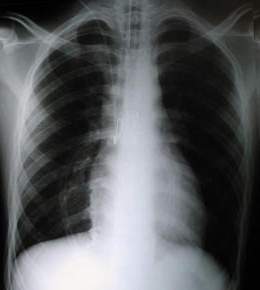

Rx PA durante terapia Intensiva

• La asistencia ventilatoria pos operatoria, con PEP fisiológico para mantener el área elevada por 2 a 4 dias, evita las complicaciones ventilatorias pulmonares. y ayuda a obtener mejores resultados.

• La radiografía anteroposterior en pos operatorio inmediato muestra al corazón en posición central, el mediastino centrado, la ausencia de neumotórax o derrame pleural, el material de síntesis esternal (alambre).

• El tubo endotraqueal, el cateter venoso central y el drenaje precostal.